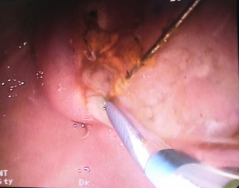

十二指肠乳头切开,脓性胆汁喷涌而出……

(EST术,即十二指肠乳头切开术) (十二指肠乳头切开后见脓性胆汁喷涌而出)